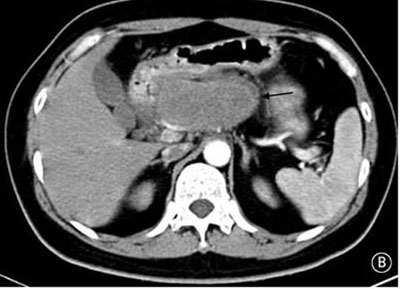

就診時實驗室檢查結(jié)果顯示嚴重高血糖(血糖水平為982mg/dL[55mmol/L])。腹部CT檢查顯示胰頭部位出現(xiàn)一個9cm大小的腫塊(如圖B箭頭所示)??崭寡逡雀哐撬厮綖?30pg/ml(正常值≤80pg/ml)。